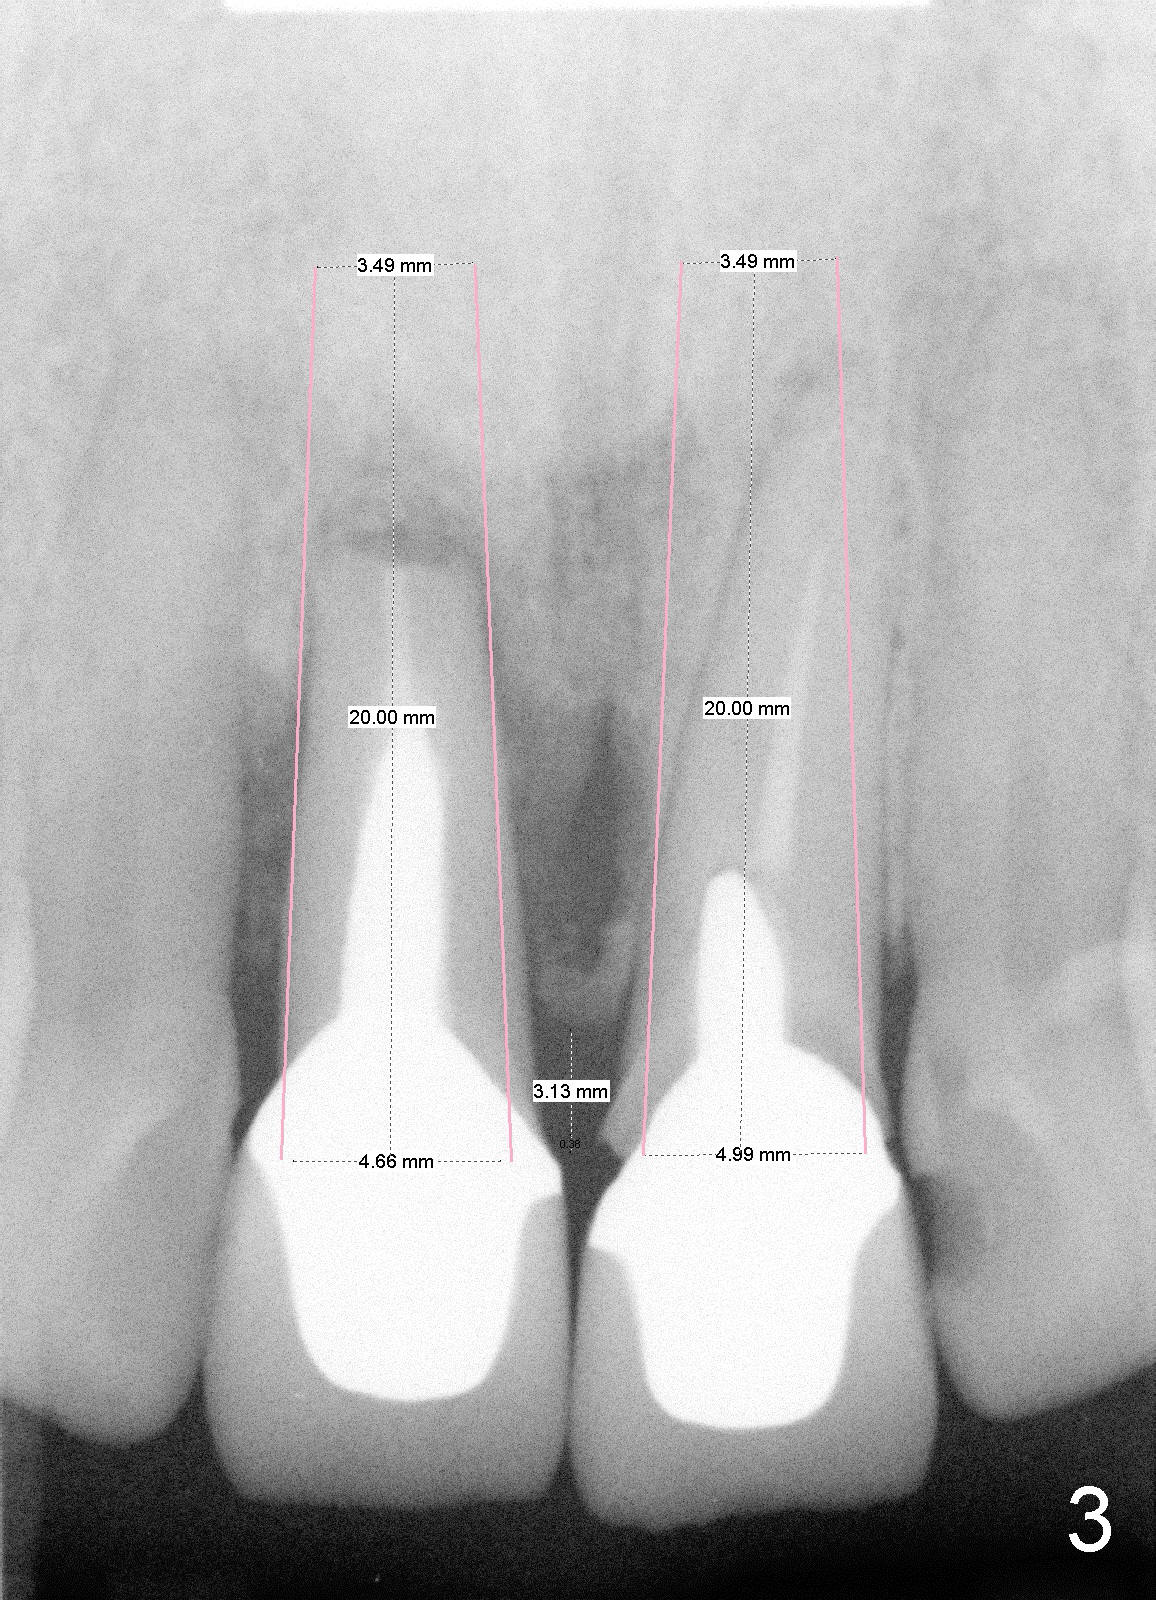

Fifty-five-year-old lady became my patient 6 years ago because of RCT for #11 (Fig.1). At that time, #8 had a large and malpositioned post (P), whereas #9 did not have a post. Since then, she has returned for recementation of crowns for several times. Recent X-ray shows that #8 has had apicoectomy (black * in Fig.2) and large radiolucency on the side of the root (white *, which was absent 6 years ago, as compared to Fig.1). The tooth #9 crown is loose with subgingival margin. It appears that both incisors are nonsalvageable.